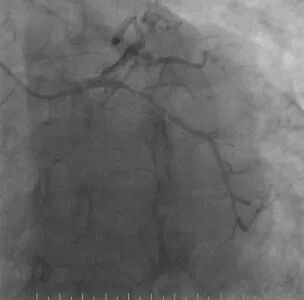

心脑联合造影

-- 右侧颈内起始部中度狭窄,经前交通向左侧代偿

波科支架怎么样​径技·第165期|7F经桡入路下的颈动脉狭窄支架成形术一例_https://www.jmylbn.com_新闻资讯_第18张

波科支架怎么样​径技·第165期|7F经桡入路下的颈动脉狭窄支架成形术一例_https://www.jmylbn.com_新闻资讯_第19张

波科支架怎么样​径技·第165期|7F经桡入路下的颈动脉狭窄支架成形术一例_https://www.jmylbn.com_新闻资讯_第20张

-- 冠脉多发狭窄